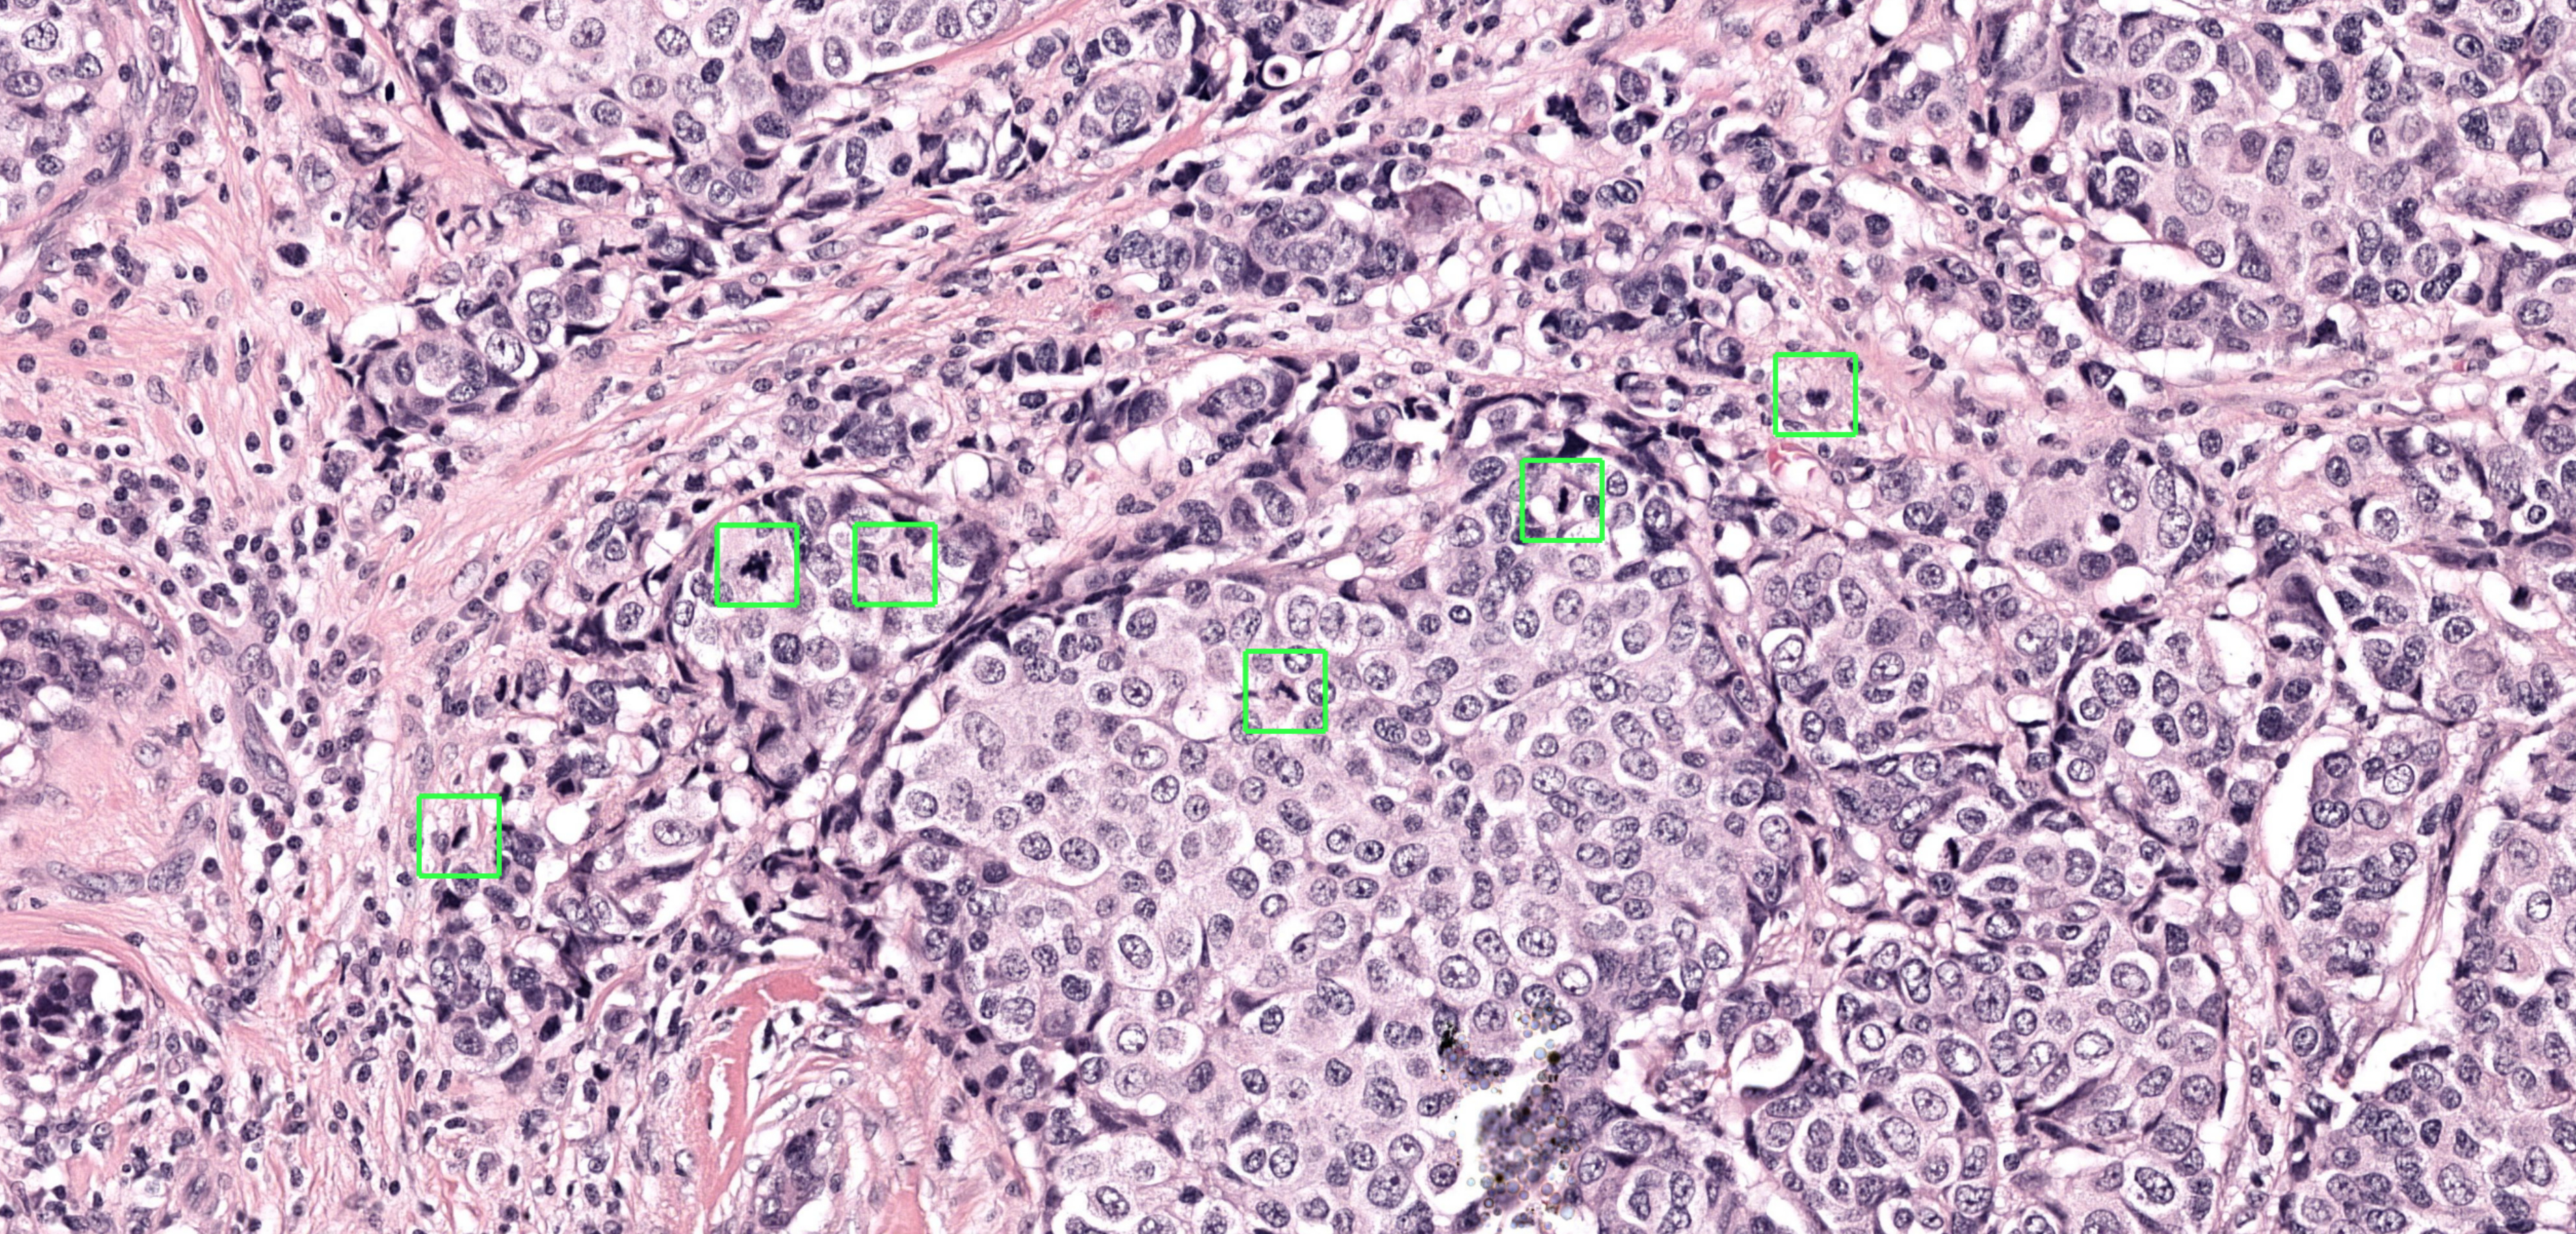

NIMEGA, Países Bajos--(BUSINESS WIRE)--Aiosyn, una empresa de software médico especializada en soluciones con IA para detectar patologías, ha presentado su primer algoritmo de IA en su familia de productos para la mitosis: Aiosyn Mitosis Research. Este novedoso algoritmo de aprendizaje profundo está diseñado para buscar automáticamente células en proceso de división (mitosis) y asistir a los laboratorios de patología de investigación con la detección de las figuras mitóticas en las imágenes de las biopsias y resecciones de cáncer. El segundo algoritmo de la familia, Aiosyn Mitosis Breast para uso diagnóstico, se encuentra actualmente en fase de validación clínica.